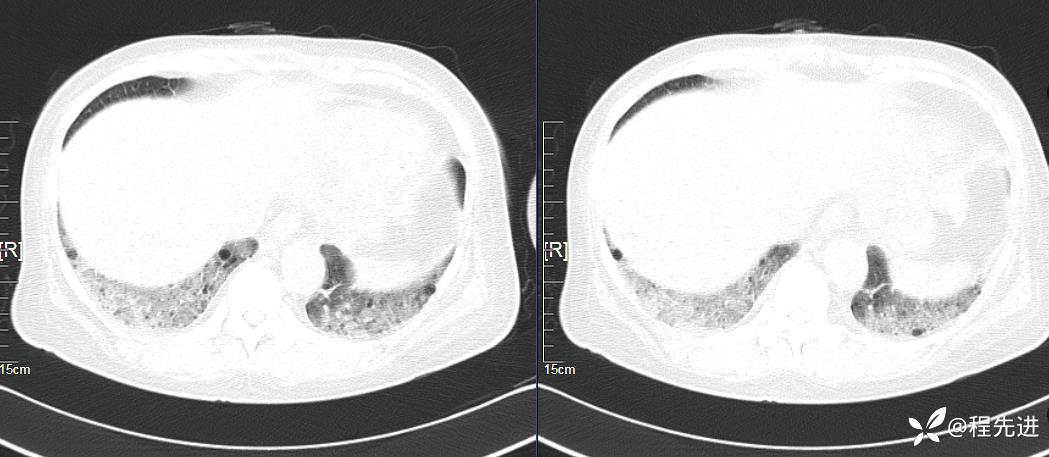

CT平扫(纵隔窗无特殊,就不上传了):

1、两肺弥漫性肺气囊的鉴别诊断有哪些?

2、本例肺气囊分布有什么特点?肺气囊有无小叶核心?有没有间质纤维化及伴发结节?